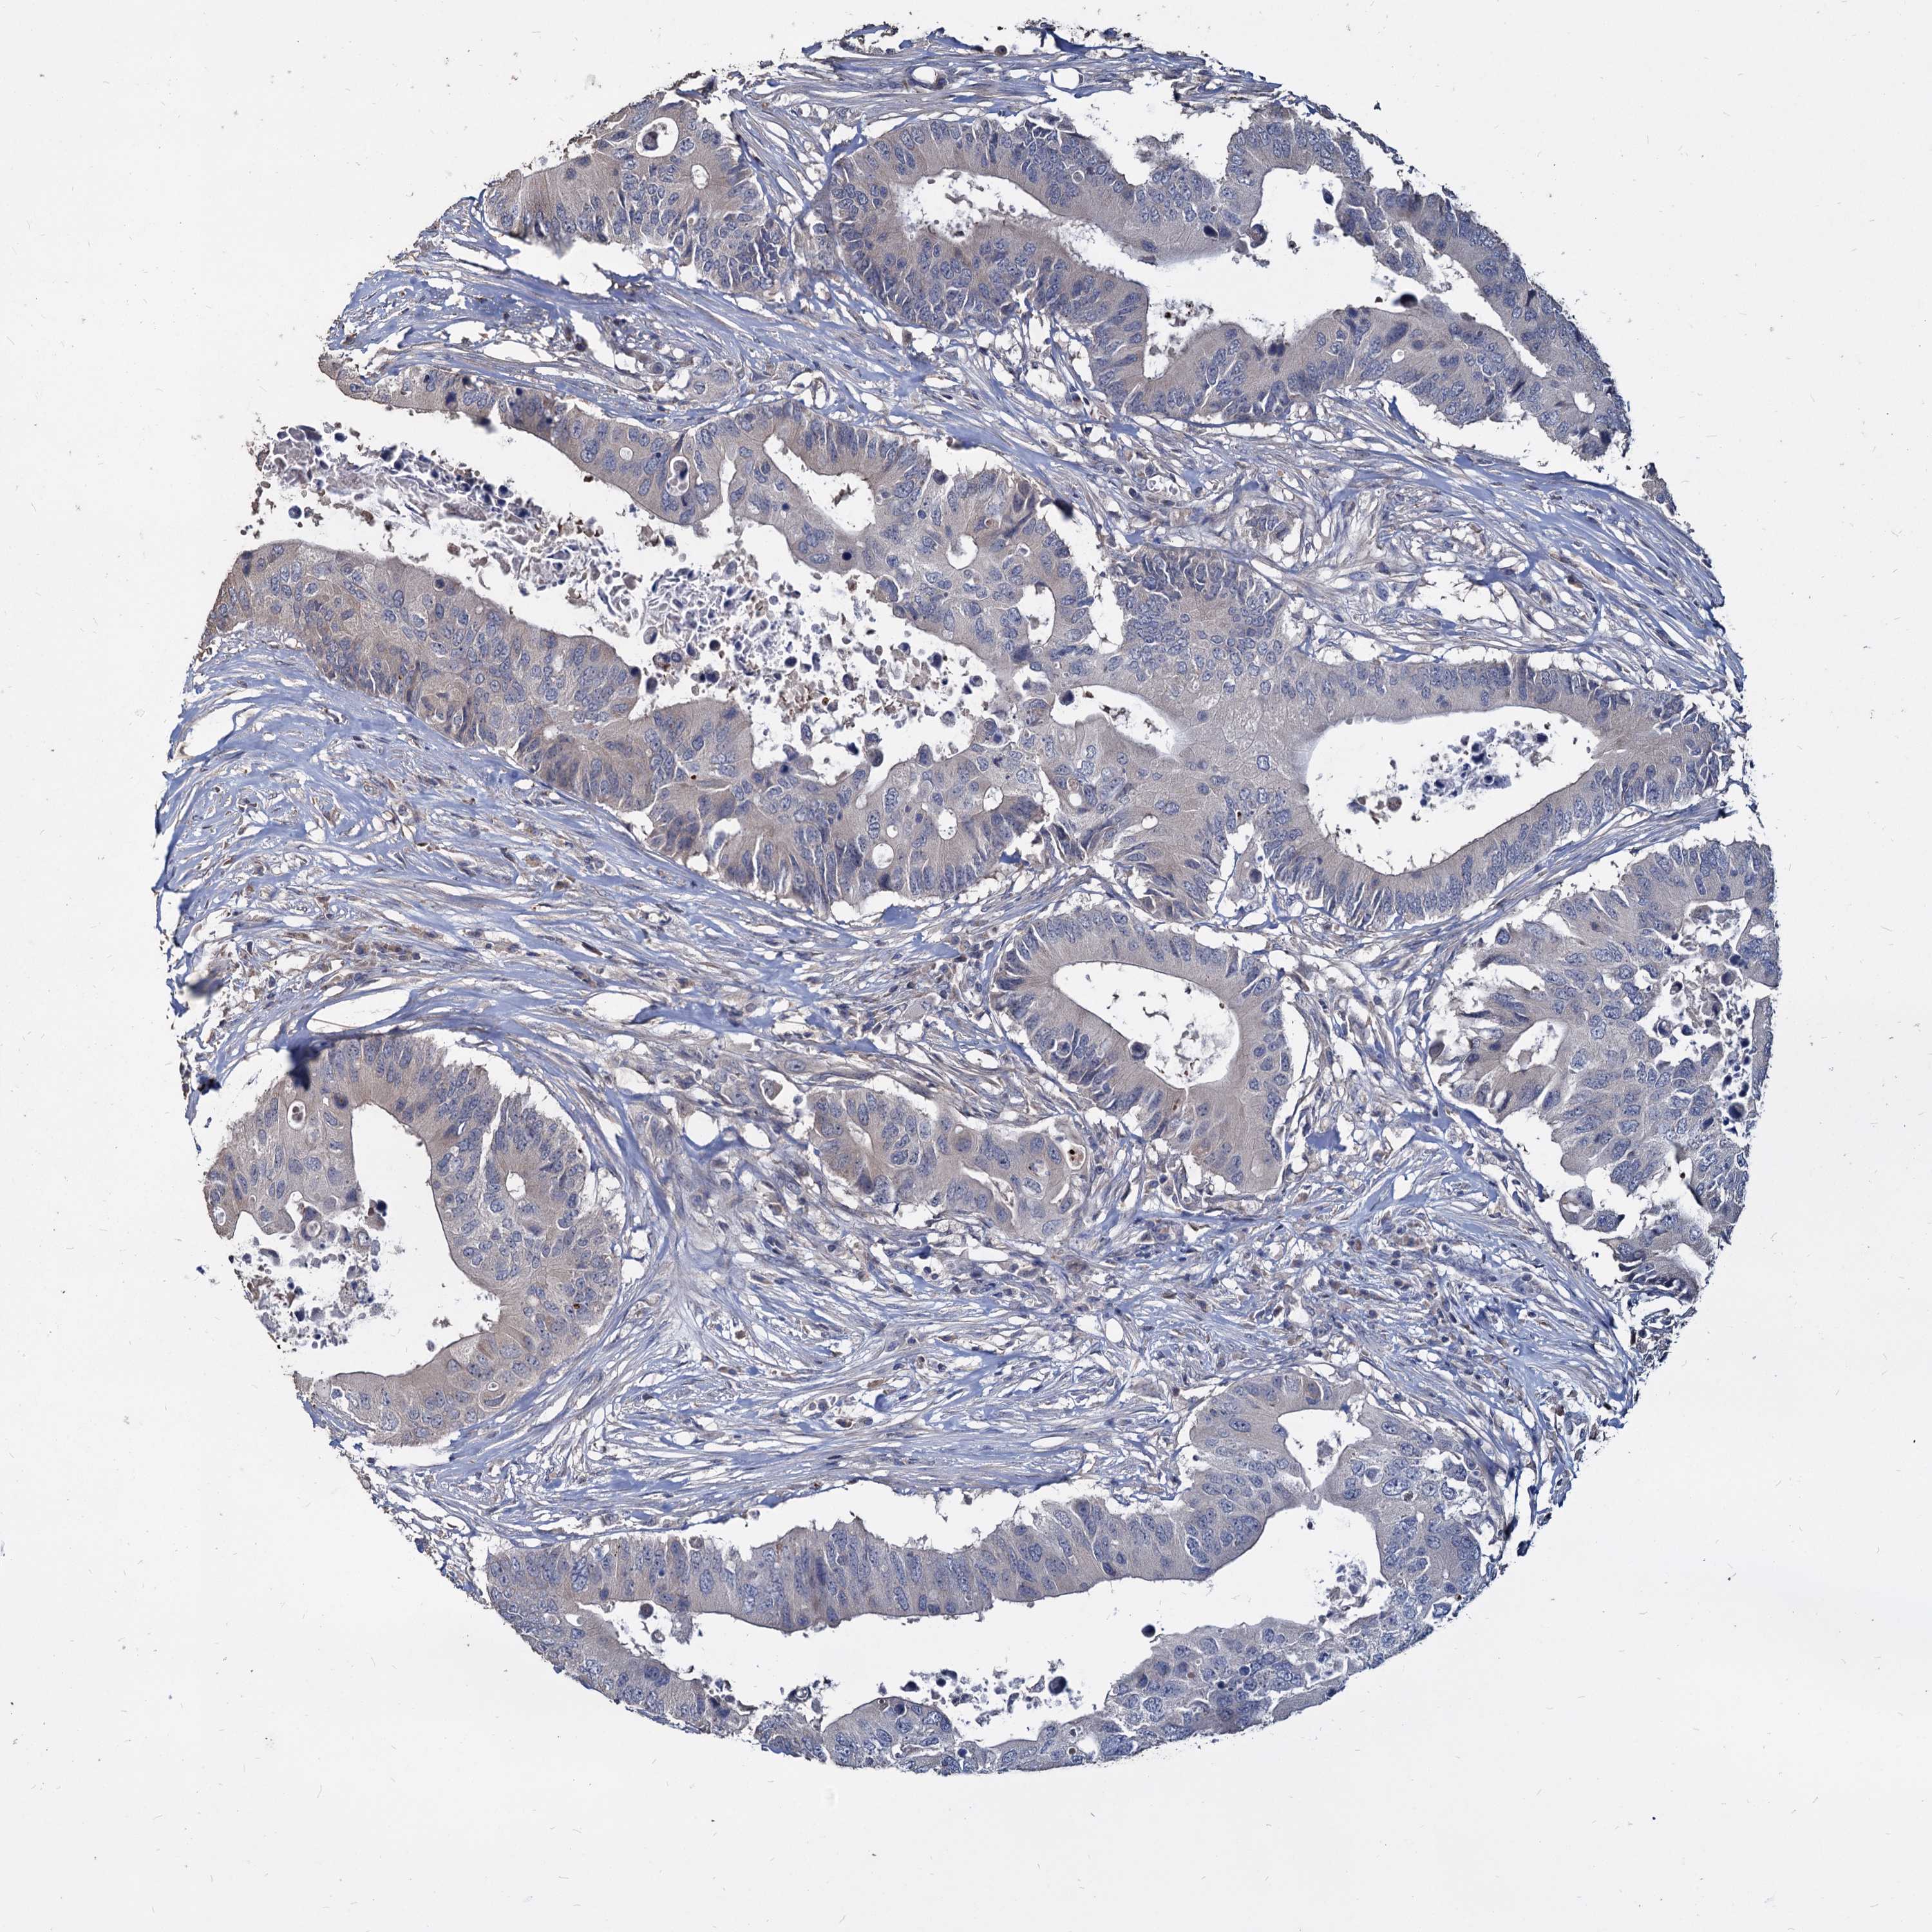

CANCER COLORECTAL CANCER Show tissue menu

Colorectal cancer

Human cancer

Colon adenocarcinoma